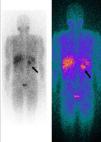

A cintigrafia de corpo com I123‐metaiodobenzilguanidina (MIBG) revelou a existência de hiperfixação nodular com aproximadamente de 3‐4cm de diâmetro a nível da suprarrenal esquerda, na mesma localização da massa observada na TAC abdominal, consistente com o diagnóstico de feocromocitoma. Não se detetavam outras zonas de hiperfixação anómalas (Figura 3).

No seguimento, não se registou evidência bioquímica ou radiológica de feocromocitoma. Do ponto de vista analítico verificou‐se normalização dos valores séricos de NT‐proBNP para valores inferiores a 20pg/mL. O ECG de Holter de 24 horas efetuado duas semanas após a cirurgia (Figura 4) demonstrou ritmo de base sinusal com FC média bastante inferior (73bpm) à do exame prévio e variabilidade da FC aumentada em relação ao basal (DPNN=97ms). Na análise da variabilidade da FC no domínio da frequência havia recuperação do componente de HF (HF=139ms2) e de LF (LF=376ms2). O ecocardiograma transtorácico efetuado dois meses depois da cirurgia revelou uma normalização das dimensões da cavidade do ventrículo esquerdo e recuperação da função sistólica ventricular esquerda (Tabela 1; Figura 3). Perante a reversibilidade do quadro clínico de miocardiopatia e encontrando‐se o doente assintomático, foi possível suspender toda a medicação em ambulatório.